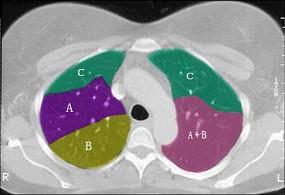

结合肺段模式心室层面(见图),选出右肺上叶的组成 ( )A、A+B+C+DB、A+B+C+D+EC、A+BD、A+B+CE、A

问题 结合肺段模式心室层面(见图),选出右肺上叶的组成 ( )

选项 A、A+B+C+D B、A+B+C+D+E C、A+B D、A+B+C E、A

答案 D